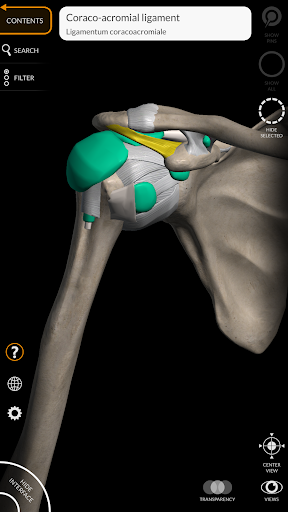

"Anatomy 3D Atlas" vous permet d'étudier l'anatomie humaine de manière simple et interactive.

Grâce à une interface simple et intuitive, il est possible d'observer chaque structure anatomique sous n'importe quel angle.

Les modèles anatomiques 3D sont particulièrement détaillés et avec des textures jusqu'à une résolution de 4k.

La subdivision par régions et les vues prédéfinies facilitent l'observation et l'étude de parties individuelles ou de groupes de systèmes et les relations entre différents organes.

MODÈLES ANATOMIQUES 3D

• Système musculo-squelettique

Ligaments ajoutés